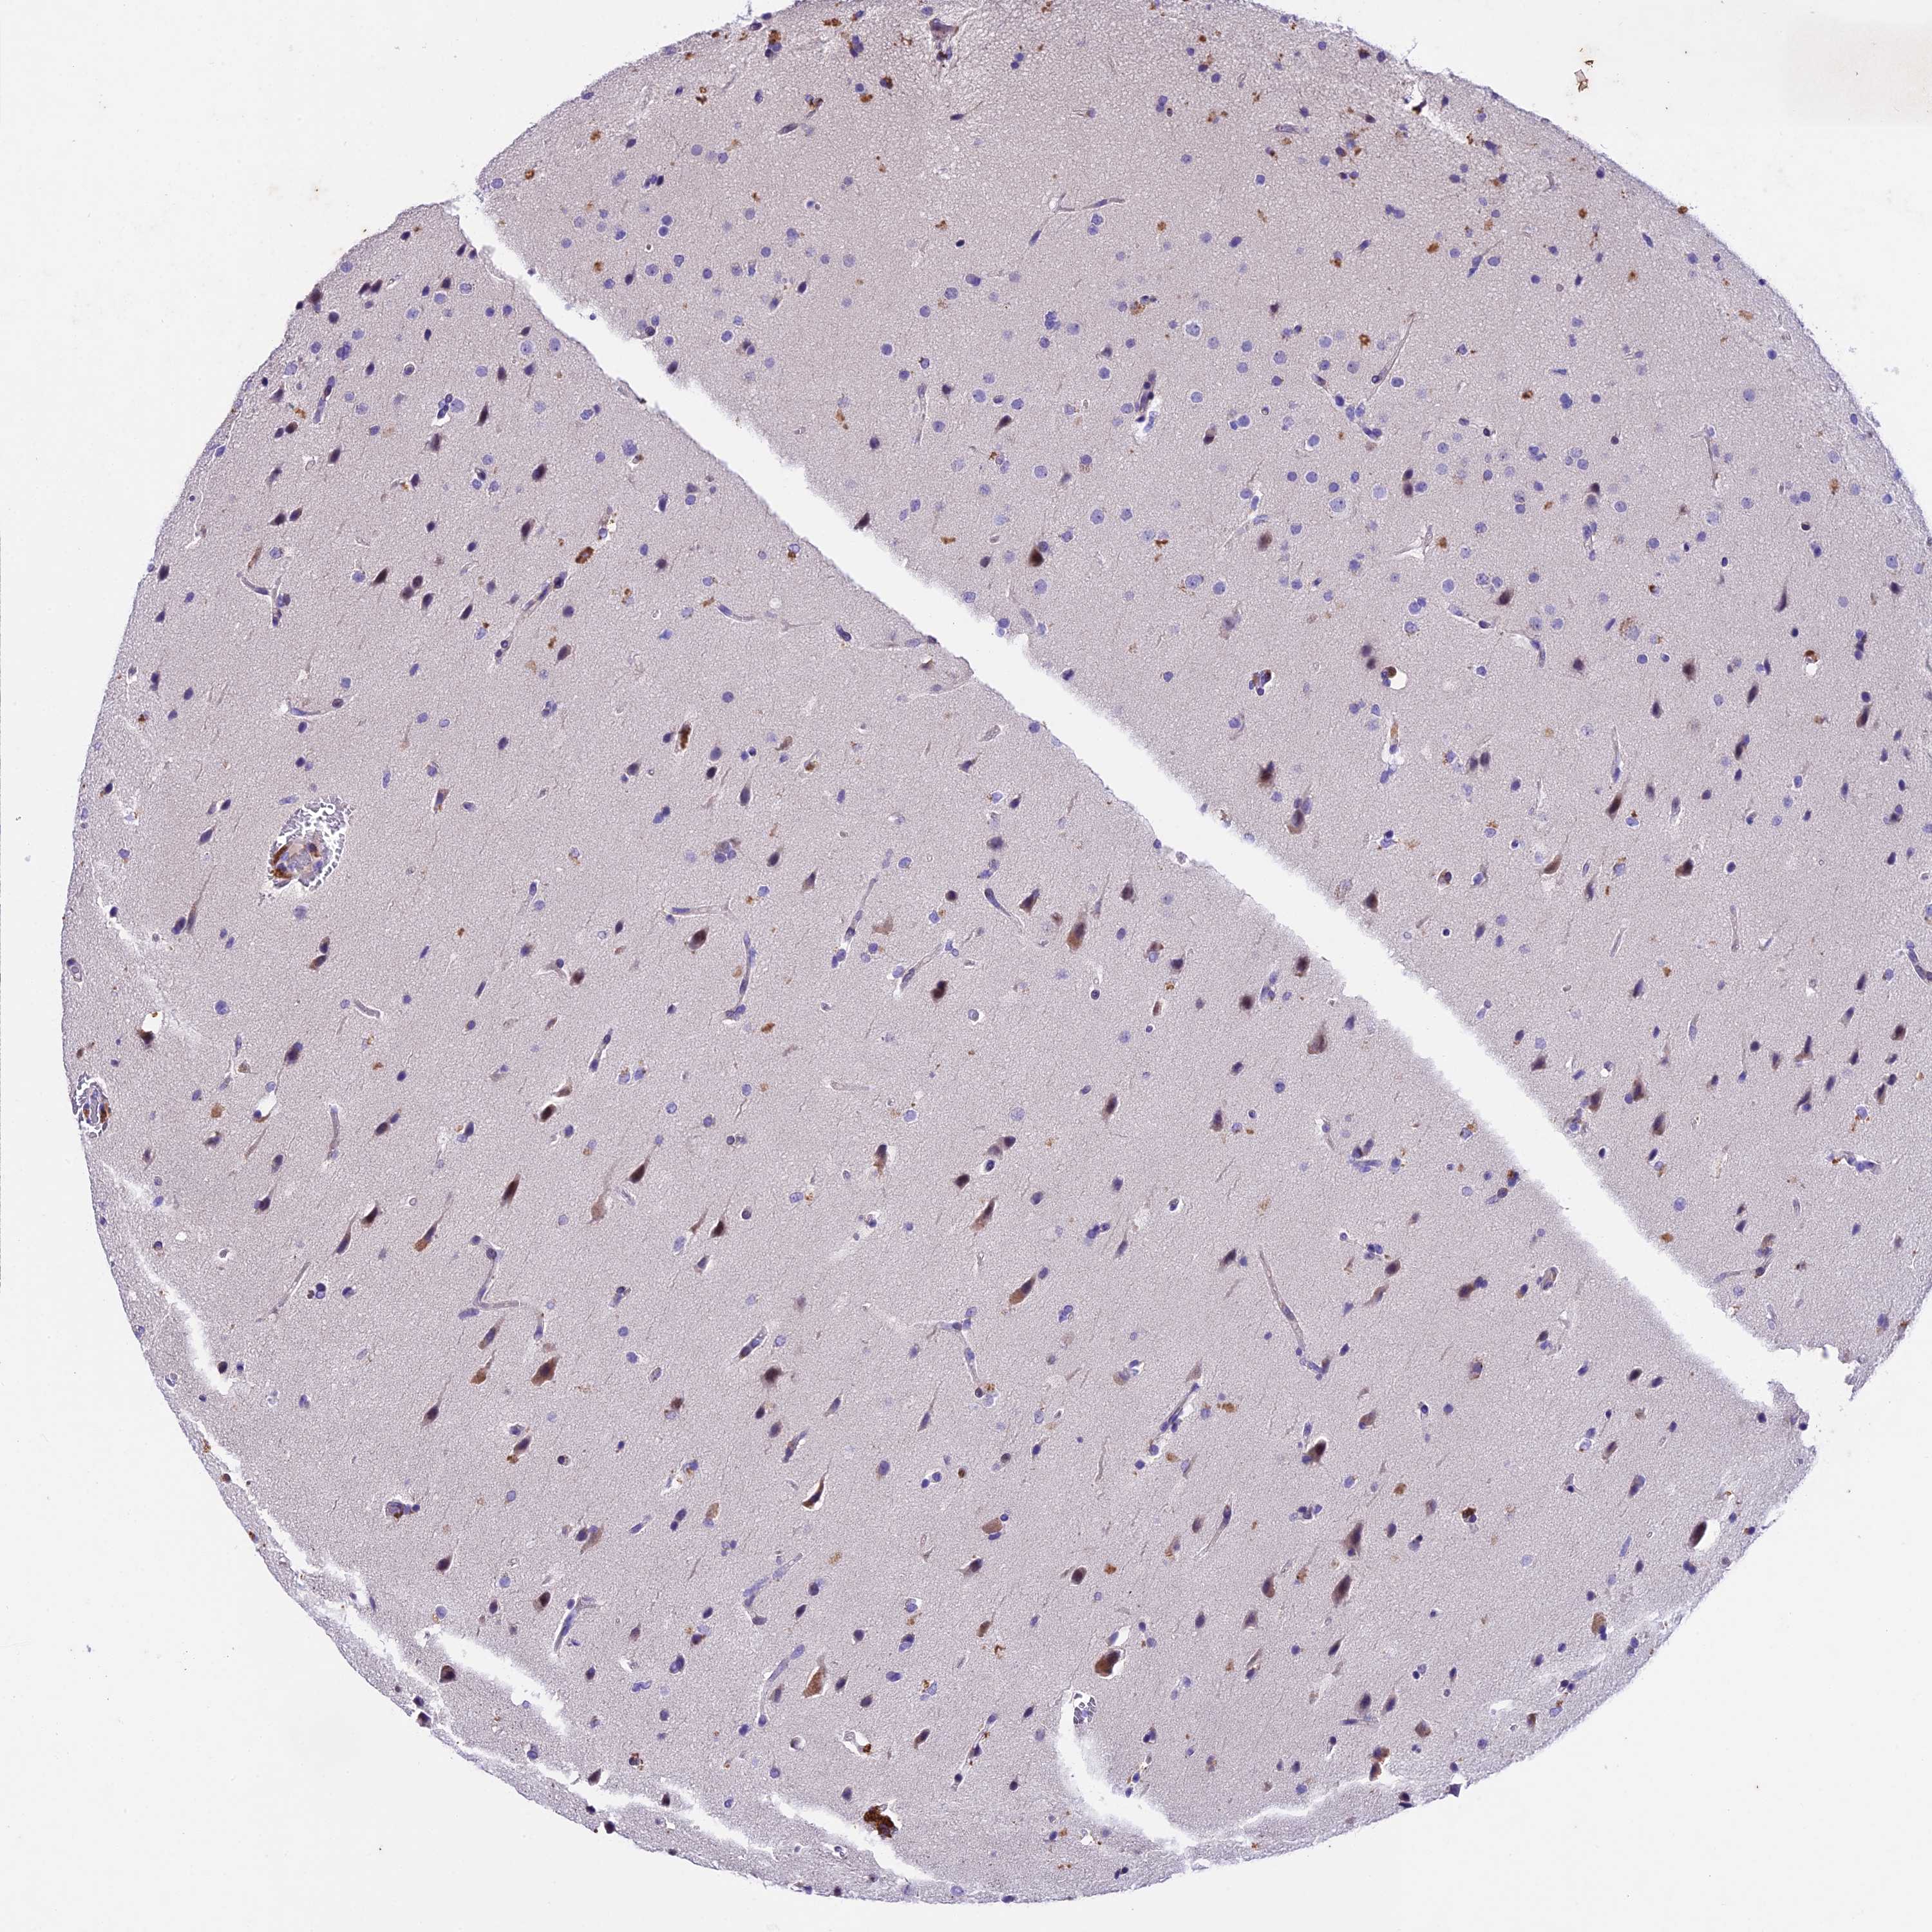

GLIOMA - Protein expressioni

A mouse-over function shows sample information and annotation data. Click on an image to view it in a full screen mode. Samples can be filtered based on level of antibody staining by selecting one or several of the following categories: high, medium, low and not detected. The assay and annotation is described here.

Note that samples used for immunohistochemistry by the Human Protein Atlas do not correspond to samples in the TCGA dataset.

Antibody stainingi

Antibody staining in the annotated cell types in the current human tissue is reported as not detected, low, medium, or high, based on conventional immunohistochemistry profiling in selected tissues. This score is based on the combination of the staining intensity and fraction of stained cells.

Each image is clickable and will lead to virtual microscopy that enables deeper exploration of all samples and also displays staining intensity scores, fraction scores and subcellular localization as well as patient and tissue information for each sample.

Antibody HPA042197

Staining

High

Medium

Low

Not detected

Intensity

Strong

Moderate

Weak

Negative

Quantity

>75%

75%-25%

<25%

None

Location

Nuclear

Cytoplasmic/membranous

Cytoplasmic/membranous,nuclear

Glioma, malignant, High grade

Glioma, malignant, Low grade

Glioblastoma, NOS